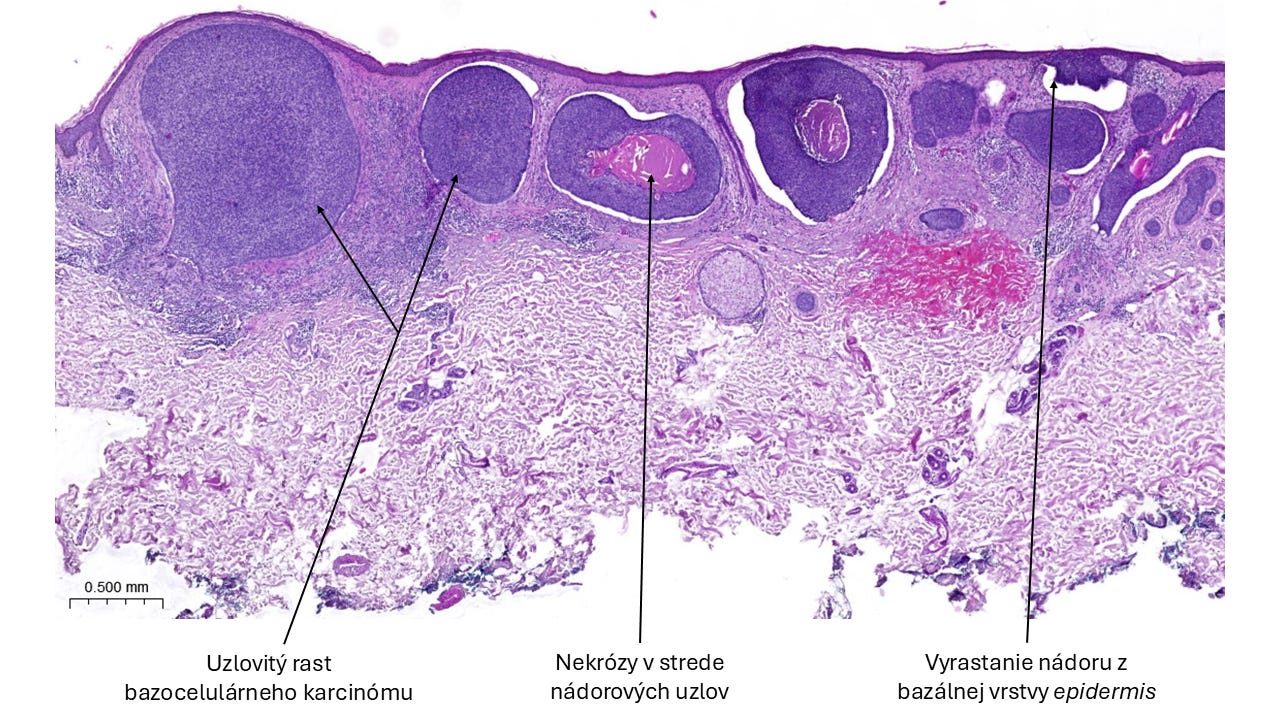

Histopatologický kvíz

📝 V dnešnom kvíze budeme cestovať v čase do 3. ročníka medicíny, na skúšku z patológie na konci letného semestra (úroveň 1/5). Toto „sklíčko” sa na skúške určite objaví, dobre si ho zapamätaj! 🤓 Odpoveď nájdeš na konci príspevku.

Riešenie histopatologického kvízu

✅ B. Bazocelulárny karcinóm (bazalióm).

💡 Ide o najčastejšie sa vyskytujúci malígny nádor kože, ktorý postihuje najmä staršiu vekovú populáciu. Podľa rizika rekurencie zaraďujeme histologické subtypy bazaliómov do skupiny s nízkym alebo vysokým rizikom. Bazaliómy sú malignity, ktoré zriedkavo tvoria metastázy.

O diagnóze si môžeš prečítať viac na PathologyOutlines. 😉